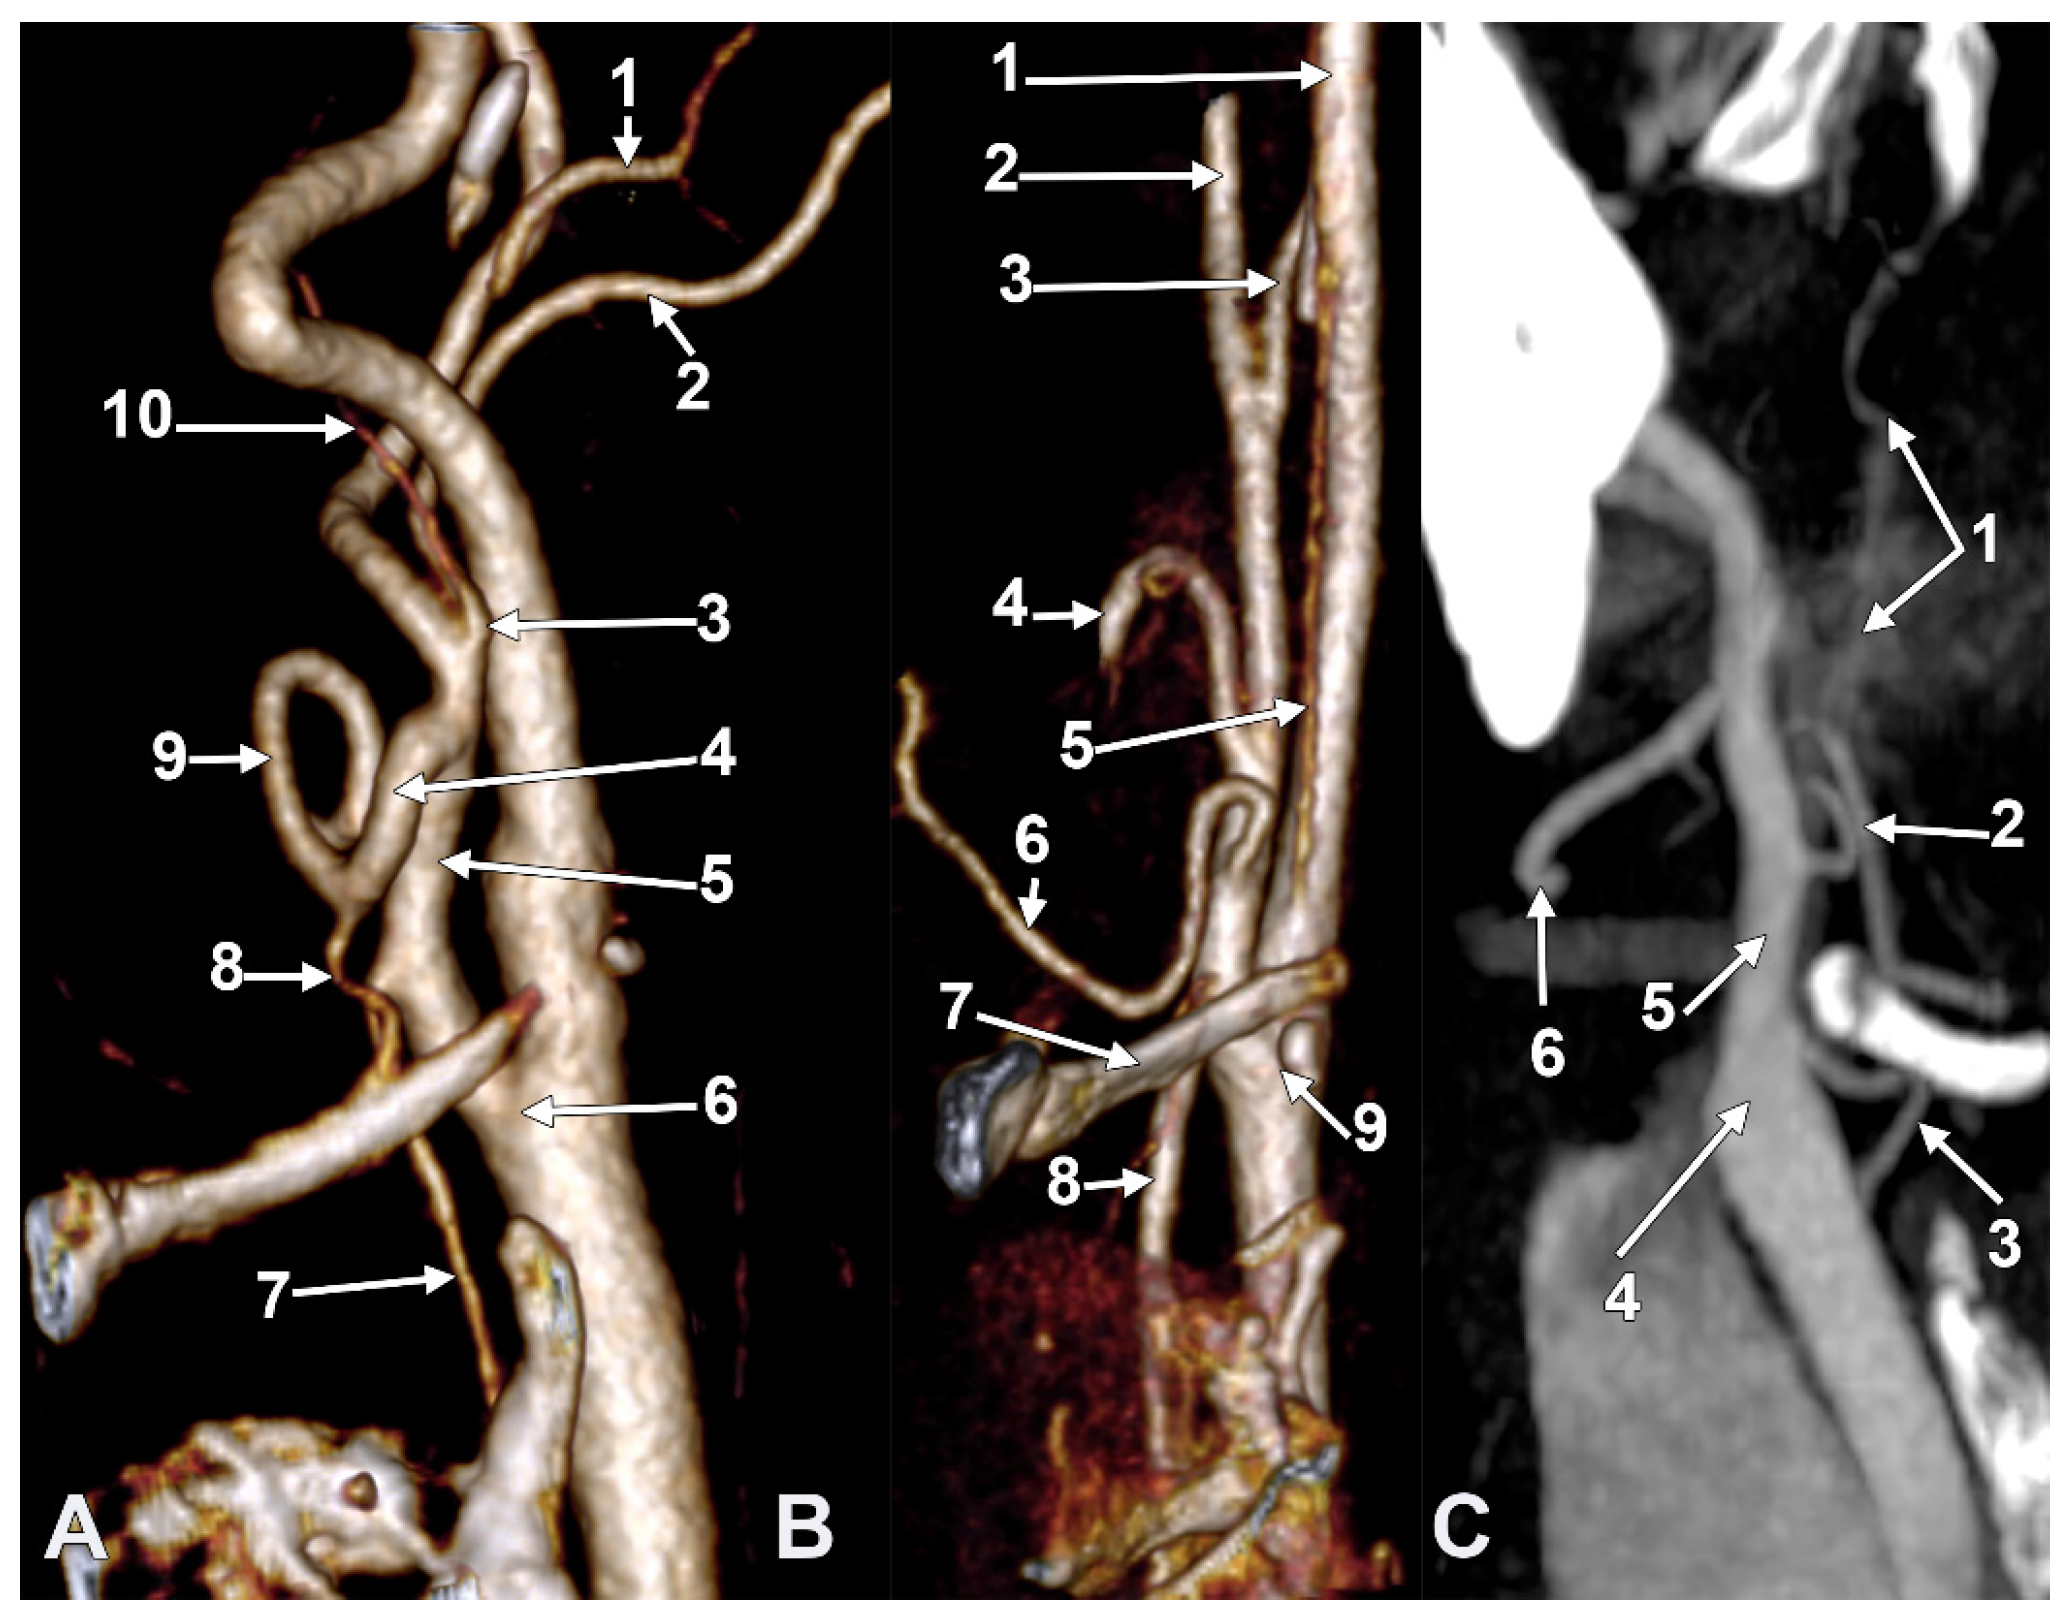

Figure 10. S-type 35 of the sequence of the external carotid artery branches. The hyoid collapsed over the thyroid cartilage of the larynx, as reported in [21]. Right side. (A) Lateral view. (B) Medial view. 1. Common carotid artery; 2. internal carotid artery; 3. external carotid artery; 4. superior thyroid artery; 5. right thyroid branch; 6. left thyroid branch; 7. thyrolingual trunk; 8. lingual artery; 9. facial artery; 10. occipital artery; 11. ascending pharyngeal artery.

In one case (Figure 10), we found on the right side the S-type 35 of APA: TLT-OA-APA-FA. On the left side, the S-type 36 was found to be absent, with STA, OA-LA-APA (with 2 roots), and FA.

The right CB was posterior to the hyoid tubercle. A 2.8 mm long TLT left the ECA immediately superolateral to the hyoid tubercle, 0.76 cm distal to the ECA’s origin. The STA thus descended over the hyoid tubercle and made a wide anterior loop, 1.53 cm anterior to the superior horn of the thyroid cartilage. The right STA then sent a right thyroid ramus to the right thyroid lobe and a left thyroid ramus to the left thyroid lobe, thus compensating for the absence of the opposite STA.

The hyoid bone was collapsed over the thyroid cartilage and tilted to the right side.